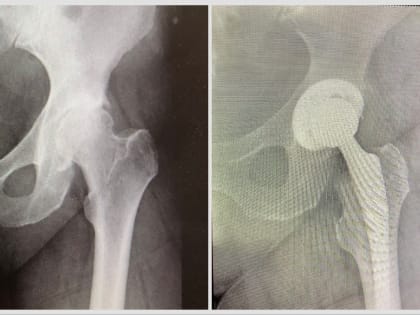

Видновские травматологи заменили сустав пациентке весом более 120 килограммов

Видновские травматологи заменили сустав пациентке весом более 120 килограммов       Врачи Видновской КБ спасли 51-летнюю пациентку с третьей стадией ожирения, у которой было дегенеративно-дистрофическое заболевание бедра.